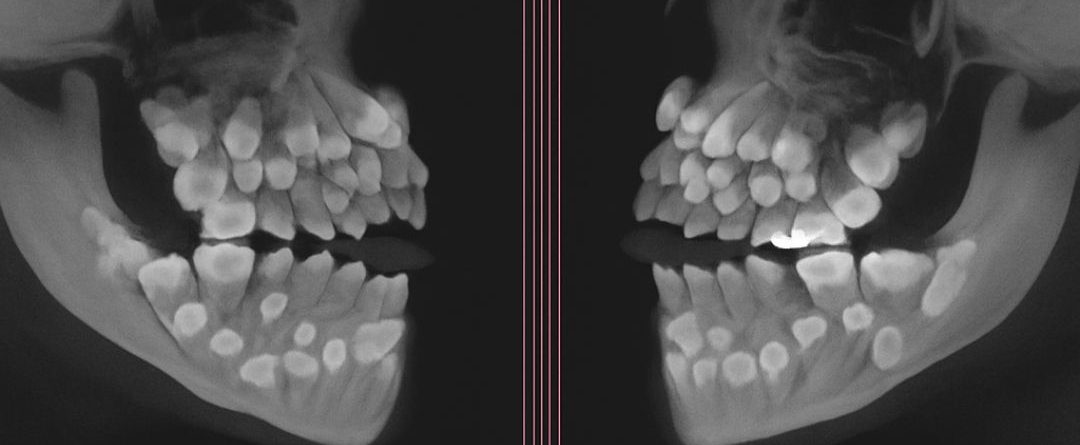

ከዚህ ቀደም ከተመዘገቡ አስደናቂ ጉዳዮች መካከል አንዱ፤ አንድ ግለሰብ 81 ጥርሶች እንደነበሩት ያሳያል፤ ይህም ከተለመደው የ32 ጥርሶች ቁጥር ከእጥፍ በላይ ነው ተብሏል።

እነዚህ ተጨማሪ ጥርሶች፣ “ሱፐርኒውመራሪ ጥርሶች” (supernumerary teeth) በመባል የሚታወቁ ሲሆን፣ በአፍ ውስጥ በማንኛውም ቦታ ሊያድጉ ይችላሉ ነው የተባለው። ብዙውን ጊዜም በቀዶ ሕክምና ማስወገድን እንደሚጠይቁ ተመላክቷል።